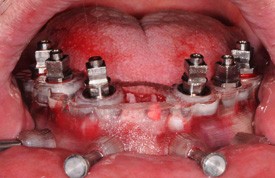

Dima chirurgica inf. posizionata in cavità orale